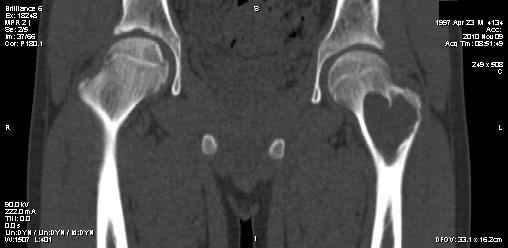

Мальчик 13 лет. В течение нескольких месяцев беспокоят боли в левом тазобедренном суставе.

При обследовании выявлена киста шейки левого бедра с сопутствующими изменениями в головке бедра, которые мы трактуем как дистрофические. Планируем вскрытие и санацию полости кисты передне-боковым доступом, костную пластику. Перед нами возникли следующие вопросы: для пластики использовать крыло подвздошной кости либо большеберцовую кость,либо их комбинацию, (полость большая,одним крылом можно не обойтись) или донорский аллотрансплантат с Коллапаном? Фиксировать ли? Если фиксировать, то чем? Доступны обычные угловые пластины либо АВФ.

Ув. Сергей! Д-з: или солитарная киста, или аневризмальная (есть небольшое "вздутие") или остеобластома ( старое название "остеобластокластома"). Если 3 вариант то полость надо обработать спиртом или азотом. Предпочтительнее аутопластика из 2 подвздошных костей. Так как срок фикс. длительный то АВФ субоптимален. Предпочтительнее фиксация угловой нестандартной пластиной 110-115 град ("разогнутая" 95 град).В запасе минимум 3 пластины с 3 типоразмерами клинка (расстояние от tuberc. innominatum до перехода метаэпифиза в нижний полюс головки).Ножка: минимум 3 винта в "здоровой" кости диафиза.Перед формированием канала пробойником 3 "страховочные" спицы: большой вертел центр головки (межвертельный перелом лучше перелома шейки) Аутопластика после МОС.

Насчёт диагноза - более чем уверен, что это солитарная костная киста. В плане лечения опимально эластичный интрамедуллярный остеосинтез стержнями или спицами без нарушения корткального слоя. Так же стандартное пункционное лечение по рекомендациям ЦИТО 85г., 90г. Берерный А.П.